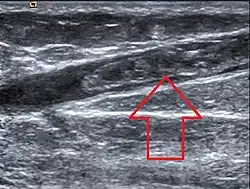

Ultrasonographic image showing thrombosis of the great saphenous vein.